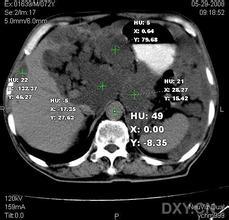

胆汁性腹膜炎胆汁性腹膜炎 在腹腔镜检查外科手术或尸检时,发现腹膜被胆汁染色的征象是诊断胆汁性腹膜炎的金试验。若从静脉注入131I-四碘四氯荧光素后从腹水中发现该物质存在有助于诊断病人是否有活动性胆漏。ERCP或术中胆道造影术时发现造影剂渗入腹腔内,有助于发现胆漏或胆道穿孔的部位。腹部X线检查是非特异性的可借此排除其他原因所致腹痛。此外CT超声波、MRI等影像学检查有助于腹部包块的鉴别诊断。